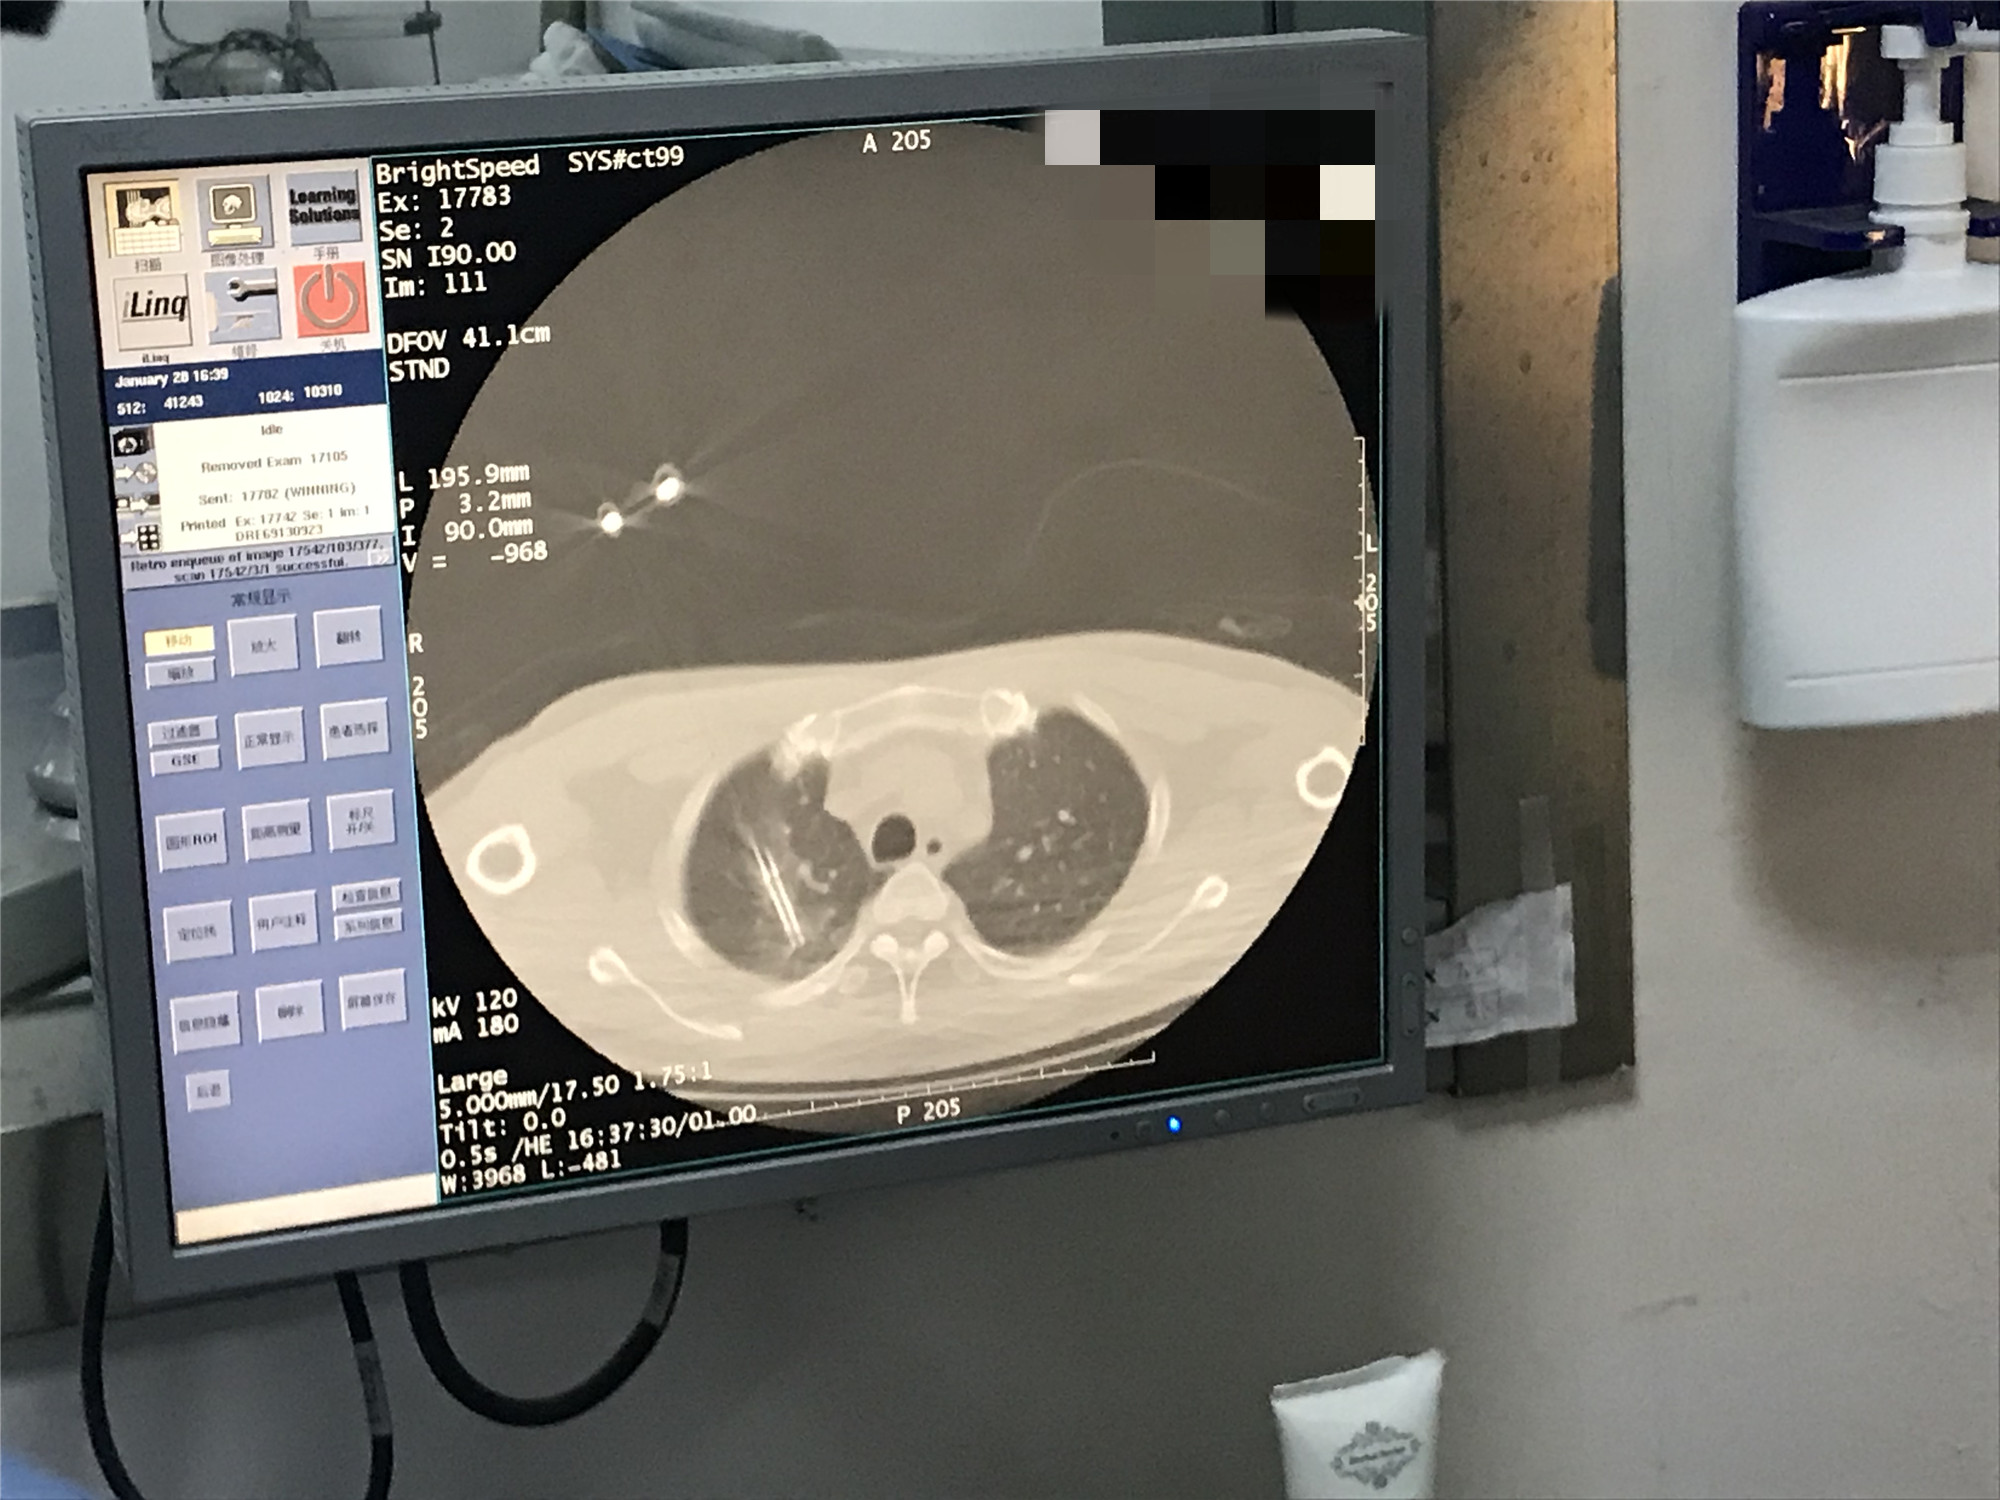

2021年1月份肺部氩氦刀手术